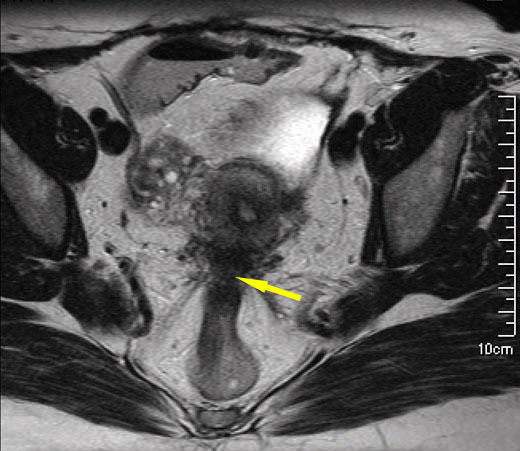

Imagerie par résonance magnétique,en coupe axiale, en pondération T2 passant par le col utérin montrant un épaississement arciforme irrégulier hypo-intense rétrocervical typique d’atteinte endométriosique du torus uterinus et des deux ligaments utéro-sacrés avec atteinte postérieure par contiguïté de la face antérieure du rectosigmoïde. Tiré de : Darai É, Bazot M, Ballester M. Endométriose. Rev Prat 2010;60:603-9.